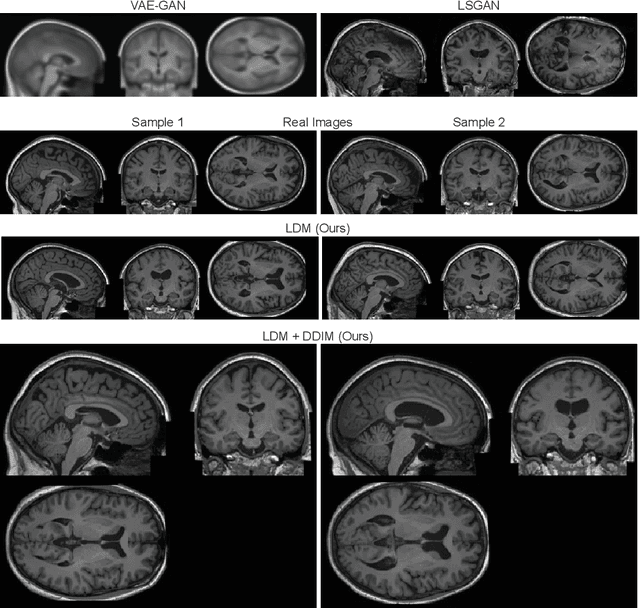

Abstract:Deep neural networks have brought remarkable breakthroughs in medical image analysis. However, due to their data-hungry nature, the modest dataset sizes in medical imaging projects might be hindering their full potential. Generating synthetic data provides a promising alternative, allowing to complement training datasets and conducting medical image research at a larger scale. Diffusion models recently have caught the attention of the computer vision community by producing photorealistic synthetic images. In this study, we explore using Latent Diffusion Models to generate synthetic images from high-resolution 3D brain images. We used T1w MRI images from the UK Biobank dataset (N=31,740) to train our models to learn about the probabilistic distribution of brain images, conditioned on covariables, such as age, sex, and brain structure volumes. We found that our models created realistic data, and we could use the conditioning variables to control the data generation effectively. Besides that, we created a synthetic dataset with 100,000 brain images and made it openly available to the scientific community.